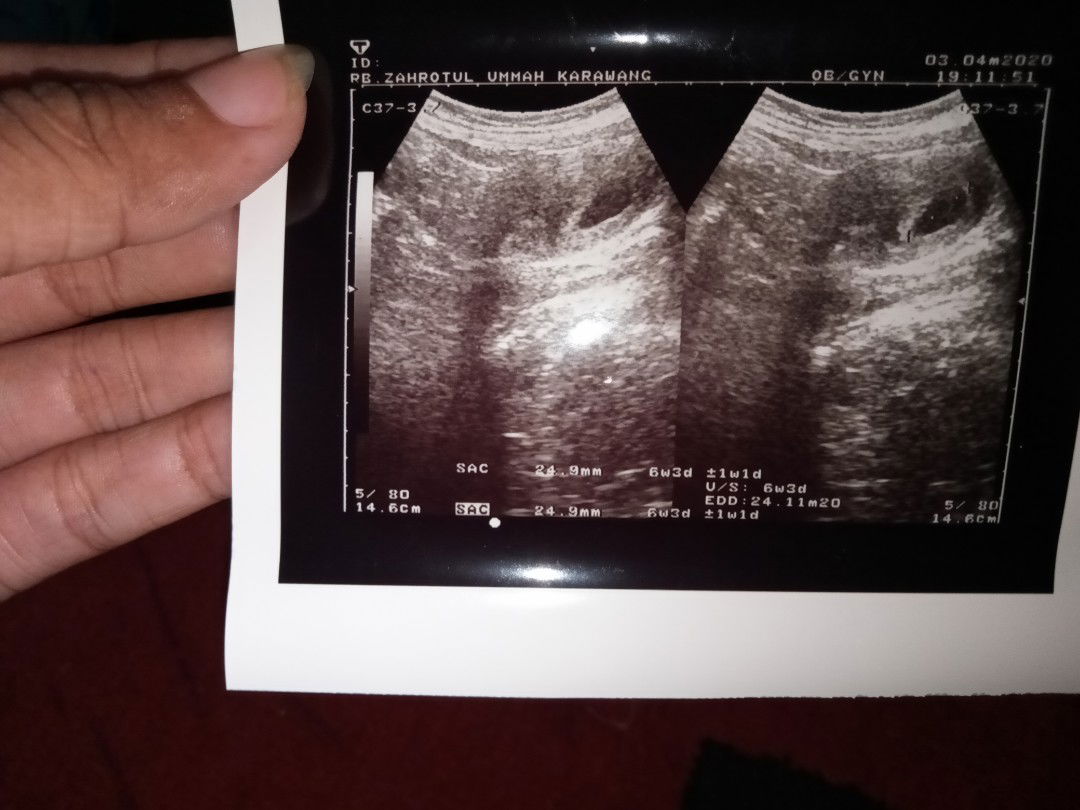

baby ga berkembng

Bunda Disni ada ga yang ke dokter atau bidan USG trus di kasih tau kalo hasil USG beda sama hitungan hpht Dan itu bedanya 2mngguan Takutnya janin TDK berkembang ( bo) Tp payudara membesar..mual seperti hamil normal... Saya riwayat keguguran 3x... Sedih ???bunda ... Menurut kalian saya harus gmn ya... Ada tau ga biar janin trus berkembang aku ingin sekali hamil dan punya anak lagi..hasil USG ku terbaru